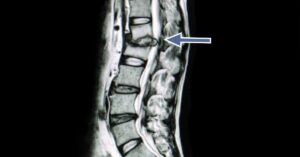

Neck pain and back pain arising from disc injuries can resolve quickly if caught early. Unfortunately, in many cases, disc injuries can take several months to recover from. Although this

Did you know that you can influence the likelihood of getting a cervical or lumbar disc herniation? You can. Making a few lifestyle adjustments can have a significant impact on